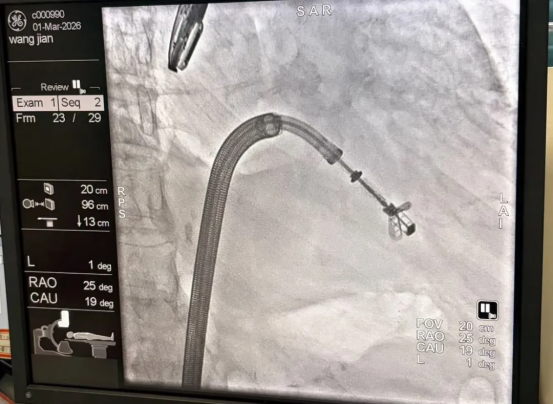

经全面评估,尚粉青主任团队决定采用DragonFly™系统进行微创介入治疗。该器械具有独立抓捕功能和中央封堵网设计,能有效降低瓣叶张力,减少残余反流。

患者二尖瓣脱垂宽度达20mm,属于广泛病变。团队迎难而上,制定多夹植入策略:首先于A1/P1区域精准植入一枚夹子,随后根据残余脱垂情况补夹一枚,最终实现对广泛脱垂区域的完美修复,术后造影显示反流消失,血流动力学显著改善。